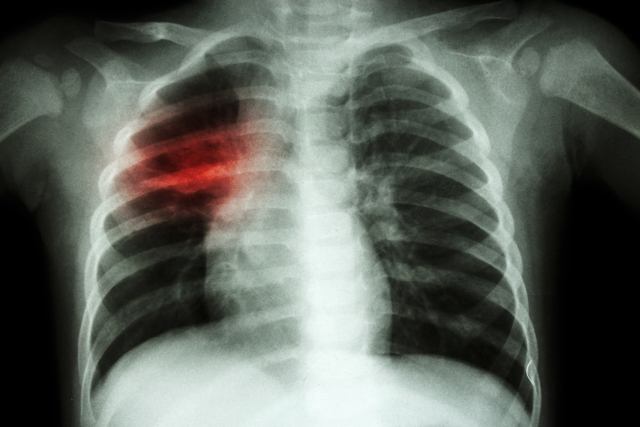

Akciğer kanseri, sık görülen ve kansere bağlı ölümlerin başlıca nedenlerinden biri olarak ülkemizde ciddi bir halk sağlığı sorunu oluşturuyor. Tıbbi Onkoloji Uzmanı Doç. Dr. Murat Sarı, bu hastalığın erken evrede tespit edilmesinin tedavi sürecinde belirleyici bir rol oynadığını ifade etti. Akciğer kanseri riskini artıran en önemli etkenin sigara kullanımı olduğunu vurgulayan Doç. Dr. Sarı, sigara içen bireylerin tarama programlarına düzenli olarak katılmasının hayati önem taşıdığına dikkat çekti.

Doç. Dr. Sarı konuşmasına şöyle devam etti: “Akciğer kanseri tanısı genellikle öksürük, kanlı balgam, nefes darlığı gibi şikayetlerle başlar. Bu şikayetler sonrası yapılan tetkikler sonucunda akciğerlerde bir lezyon görülmesi durumunda, hastaya bronkoskopi eşliğinde veya dışarıdan bir iğneyle biyopsi alınarak tanı konur. Tanıdan sonra hastanın evrelemesi yapılır ve tedavi süreci buna göre belirlenir. Erken evre akciğer kanserinde, hastalığı tamamen yok etmek amacıyla cerrahi müdahale yapılabilirken, ileri evrelerde tedavi daha çok hastalığın kontrol altına alınması ve hastanın yaşam süresinin uzatılması hedeflenir.”